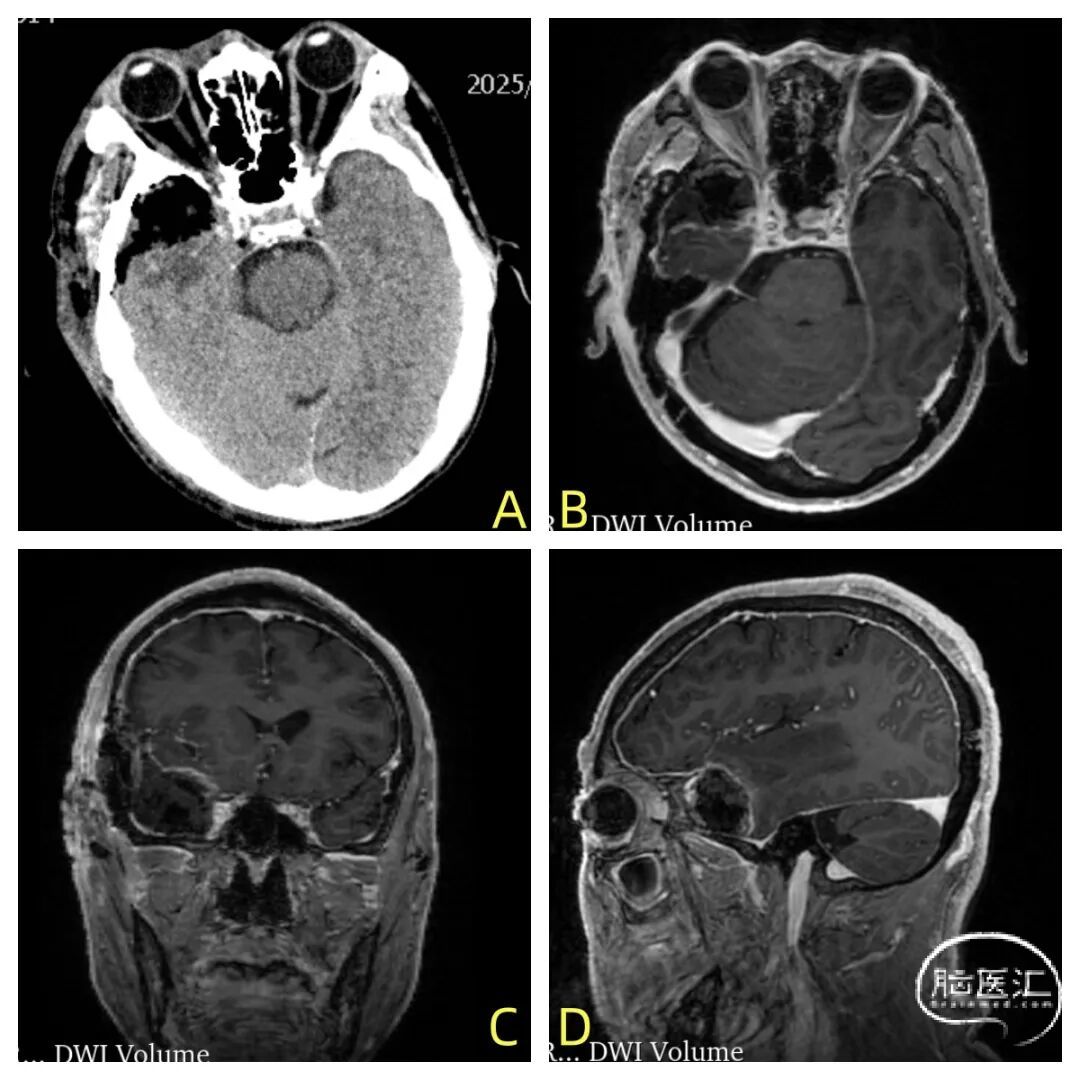

入院后,李主任为患者安排了更精确的头颅核磁平扫+增强检查。影像结果显示:右侧中颅底颞部颅板下可见一大小约2.7cm×2.4cm×2.5cm的占位性病变。李晓东主任仔细阅片后,准确判断其为脑膜瘤的可能性大。

▲术前影像学资料:图A为术前头颅CT, 箭头处为异常水肿,图BCD为头颅核磁增强轴冠矢状位,箭头处为肿瘤。